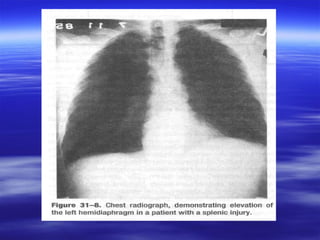

Direkt Grafi:

 Akciğer grafisi

 Pelvis grafisi çekilebilir.

 Künt travmalarının akciğer grafisinde

diyafragma veya içi boş organ

yaralanmasına ait serbest hava ve

diafragma elevasyonu görülebilir.